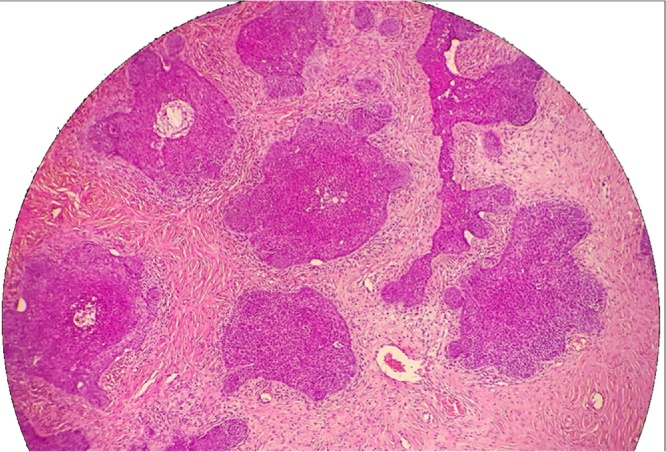

Clinical diagnosis of PNS was done and excisional biopsy was performed under general anesthesia. Fig. 1 shows the gross appearance of the specimen. The result of the histopathological examination showed focal erosion of the epidermis overlying multiple clusters of polygonal basaloid cells with dark hyperchromatic ovoid uniform nuclei extending from epidermis into superficial dermis, displaying peripheral nuclear palisades and artefactual separation stromal cleft (Fig. 2, Fig. 3). The picture was suggestive for BCC.

Fig. 2.

Multiple clusters of polygonal basaloid cells.

Fig. 3.

Polygonal basaloid cells with dark hyperchromatic ovoid uniform nuclei displaying peripheral nuclear palisades and artefactual separation stromal cleft.